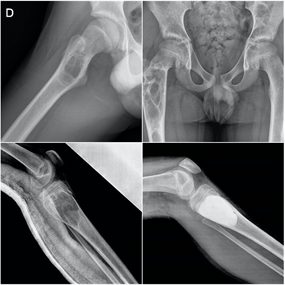

El 80% de las metástasis óseas se relacionan, por orden de frecuencia con el cáncer de mama, pulmón, próstata y riñón. Las metástasis óseas que se localizan en huesos largos suelen localizarse en el fémur, con especial predilección por la zona de la cadera.

El fémur es la localización principal, con predominio de la zona de la cadera. Otras localizaciones son la columna vertebral, la pelvis, los huesos planos y el húmero. En la espalda el dolor suele estar presente antes que los cambios radiográficos, mientras que cuando el dolor se localiza en los huesos largos suelen ya existir lesiones con riesgo de fractura.

En el cáncer diseminado el tratamiento de las metástasis suele ser paliativo, mediante estabilización de la fractura con osteosíntesis o implante de prótesis. En ocasiones la osteosíntesis se suplementa con aporte de cementos biológicos para aumentar la estabilidad o se realiza radioterapia complementaria. En casos de metástasis únicas, el tratamiento quirúrgico radical de la metástasis puede estar indicado, lo que hace necesaria la valoración conjunta de traumatología oncológica y oncología médica ante la detección de una lesión metastásica ósea en nuestra práctica.

Ante la sospecha de una fractura patológica de origen metastático debemos tener un enfoque multidiscilplinar, tanto traumatológico como oncológico, con fin de realizar tanto el tratamiento específico de la fractura como el estadiaje oncológico.